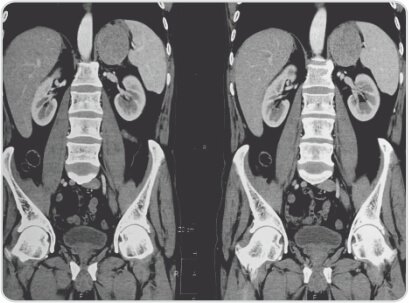

CT report shows evidence of well defined homogenous dense soft tissue lesion with few central hypodensities involving body and medial limb of left adrenal gland of 62x49x55mm, abutting lower pole of spleen, greater curvature of stomach and upper pole of left kidney.

Left adrenal mass with solid and necrotic areas – Left Adrenal Cortical Carcinoma.

Right kidney, right adrenal, liver, spleen, pancreas and gall bladder normal.

Axial and Coronal ct scan image showing left adrenal tumour